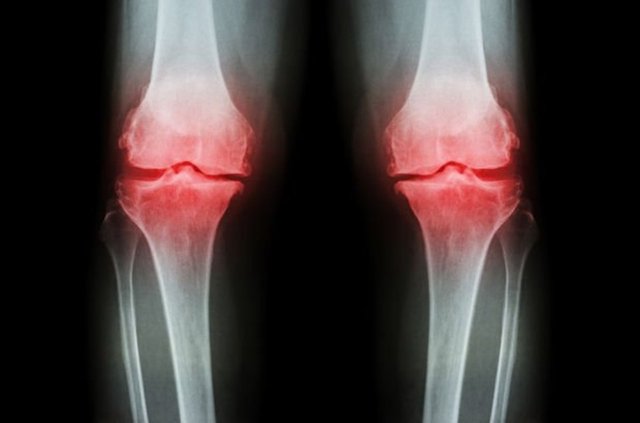

1- Kırık: Osteoporoz sonucunda üzerine yük binen kol veya bacaktaki uzun kemikler ile omurgayı oluşturan omur kemiklerinde çeşitli düzey ve şiddetlerde çatlama veya kırıklar meydana gelebilir.

4- Şekil bozuklukları: Kemiklerdeki kırılma düzeyine bağlı olarak uzun kemiklerin şekillerinde bozulmalar gelişebilir.

8- El bileklerinde kırıklar

9- Kaburga ve kalça kemiklerinde kırıklar

11- Yaygın kemik ağrıları ve kemiklerde hassasiyet